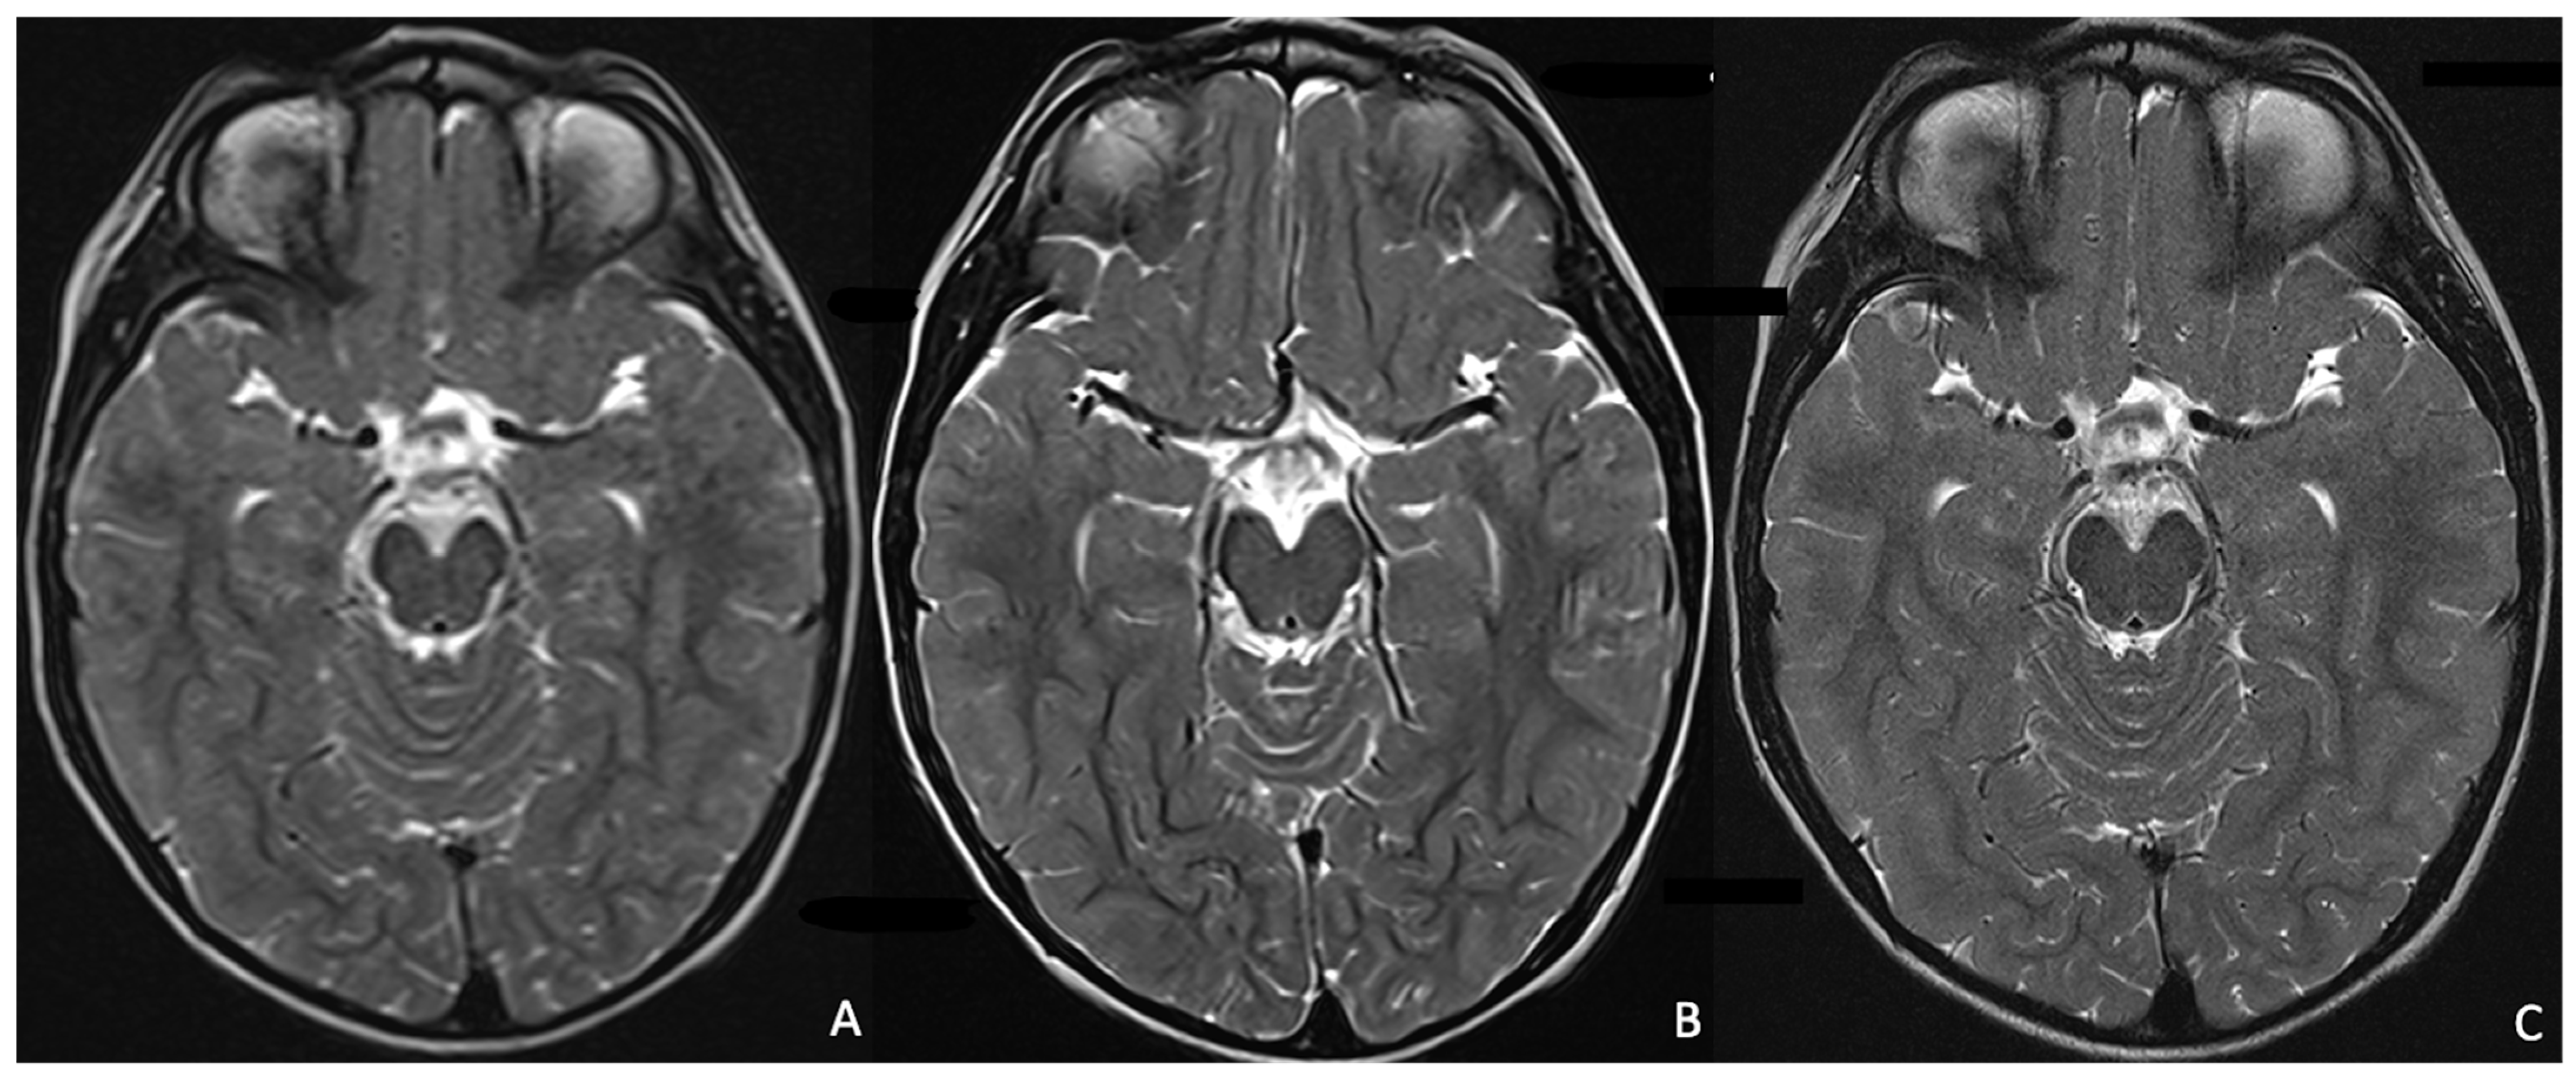

- Kim, S.-H.; Choi, Y.H.; Lee, J.S.; Lee, S.B.; Cho, Y.J.; Lee, S.H.; Shin, S.-M.; Cheon, J.-E. Deep Learning Reconstruction in Pediatric Brain MRI: Comparison of Image Quality with Conventional T2-Weighted MRI. Neuroradiology 2023, 65, 207–214. [Google Scholar] [CrossRef] [PubMed]